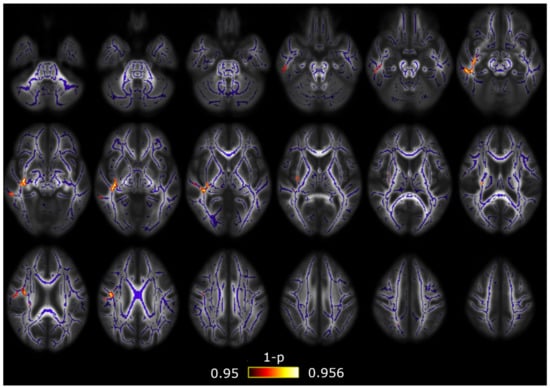

3.1. TBSS

3.2. TBSS with Covariates